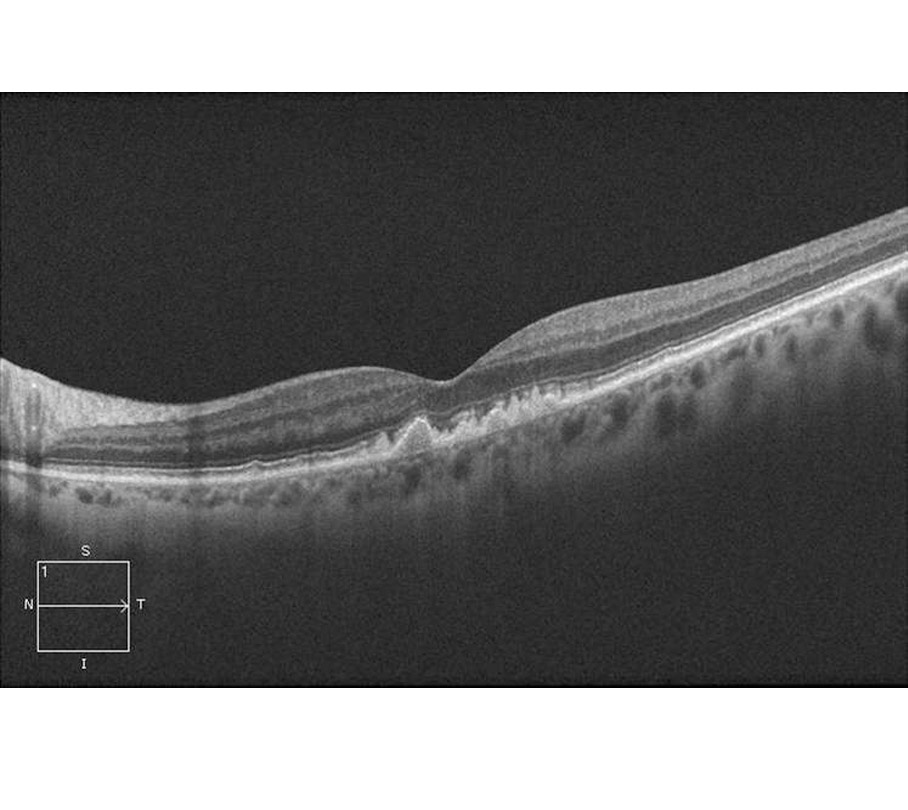

OCT-Schnittbild bei trockener AMD

Das OCT-Bild der Netzhaut ähnelt einem Ultraschall-Bild, nur wird es mit Licht statt mit Ultraschall aufgenommen. Es ist eine Art "Durchleuchtung der Netzhaut", eine "Schichtaufnahme der Netzhaut". Das OCT verwendet aber ungefährliches Infrarot-Licht und hat eine Auflösung der Gewebemessung von 5 µm. Damit kann man die Ablagerungen bei trockener AMD (Drusen), die Schicht der Nervenfasern und die Photorezeptoren erkennen.